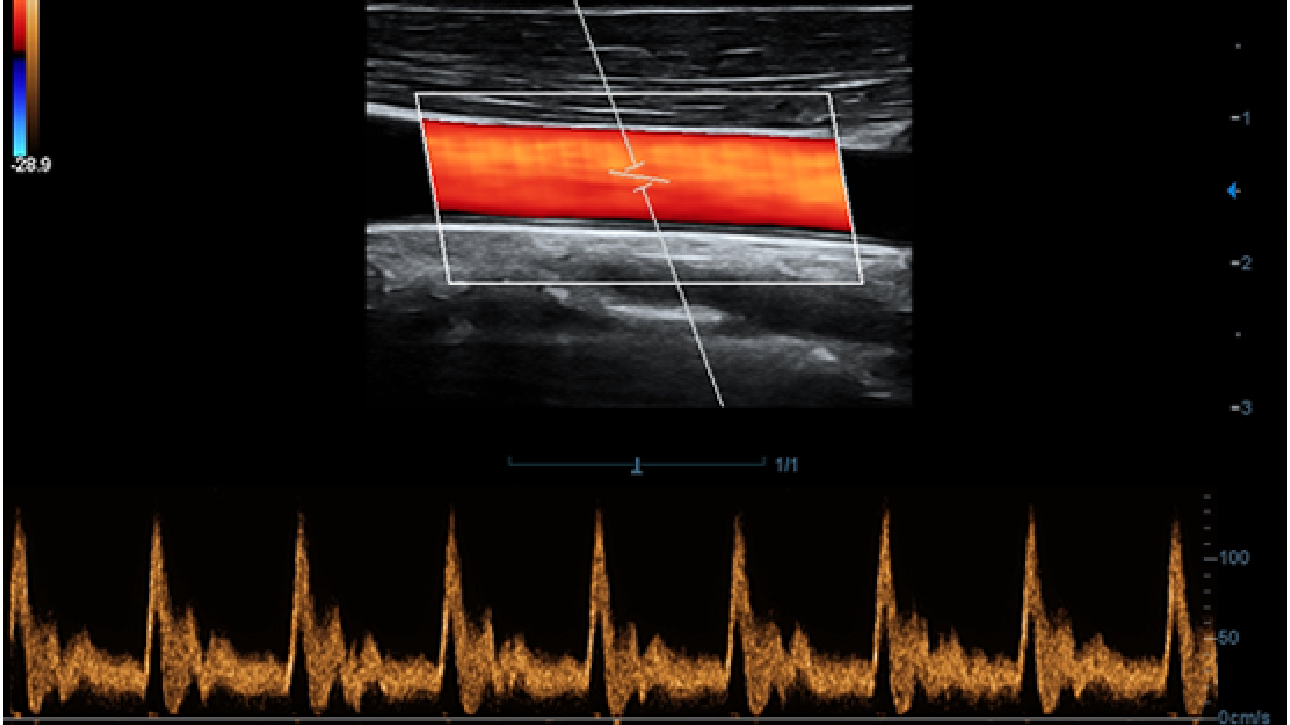

X-Insight to rozwi?zanie umo?liwiaj?ce wnikliw? analiz?, zapewniaj?c bardziej szczeg├│?owy obraz.

Opieraj?c si? na analizie potrzeb klienta, DC-60 Exp X-Insight zosta? zaprojektowany tak, aby znacznie usprawni? diagnostyk?, kt├│ra jest wspomagana przez technologi? eXpress Clarity, eXceptional Intelligence i eXceeding Experience.

Obrazy kliniczne